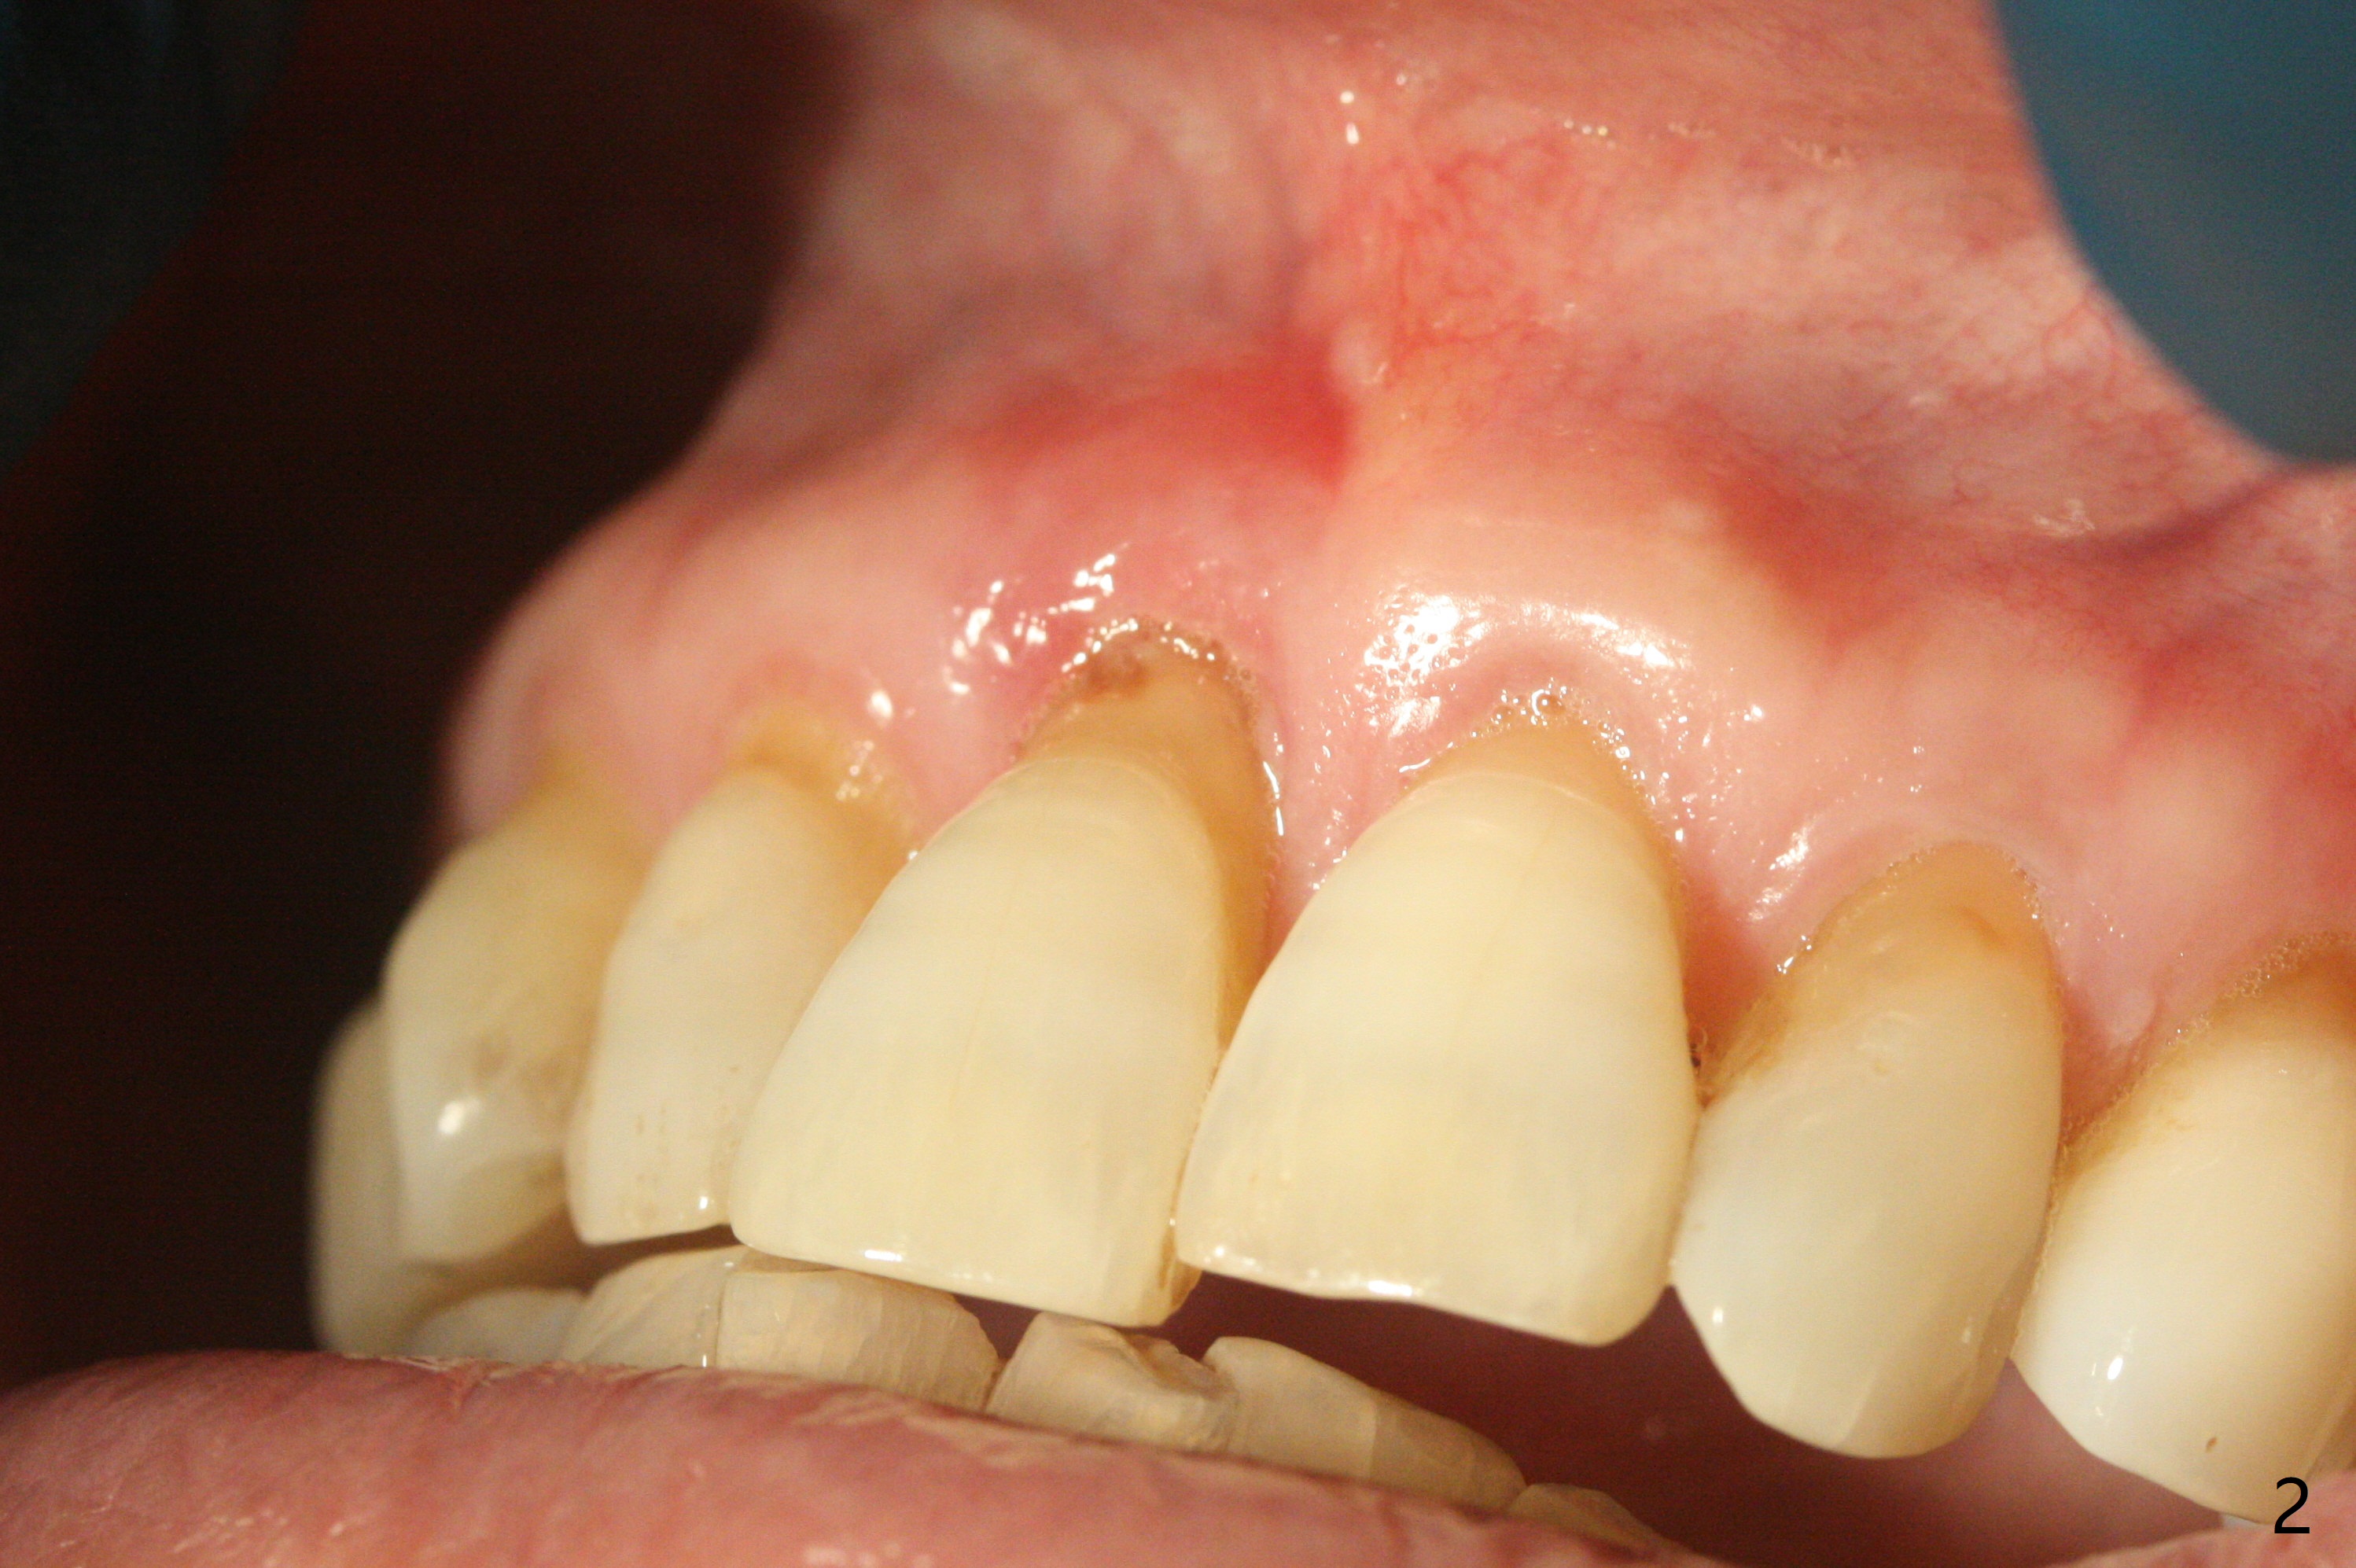

59岁女今天就诊,“上门牙快掉下来”,检查表明右上1延长(图一:长箭头),牙龈退缩(短箭头),红肿(*),颊侧骨板触诊不觉得塌陷(图二)。咬合时,患牙前移(图三),伸长的下切牙(图三,九:1,2)造成咬合创伤。因此拔牙前,将降低下门牙切缘(图四,五(黑色)),为临时牙冠创造足够修复空间。CT冠状切面显示颊侧(图六:B)骨板缺失,可以植入两段式植体(3.5x11.5 毫米),但是最细基台(4毫米直径,图七(粉红色和蓝色))显得太粗,不利于腭侧修复空间形成,而2.5x14(4)毫米一段式植体不仅创造更多颊侧植骨空间(图八(红箭头)),而且由于固有基台直径小(白箭头),容易形成腭侧修复空间。一旦前牙植体永久性修复完成,督促病人做三个第二磨牙植牙修复(图九:7),减少对前牙植牙创伤。临时牙冠不仅解决美观问题,而且固定骨粉,保持颊侧骨板隆起,维持牙龈缘和乳头。在大多数情况下,使用现成树脂牙冠(crown form)制作临时修复物,这个病例牙齿完整,截除的牙冠可以用来做临时牙冠。